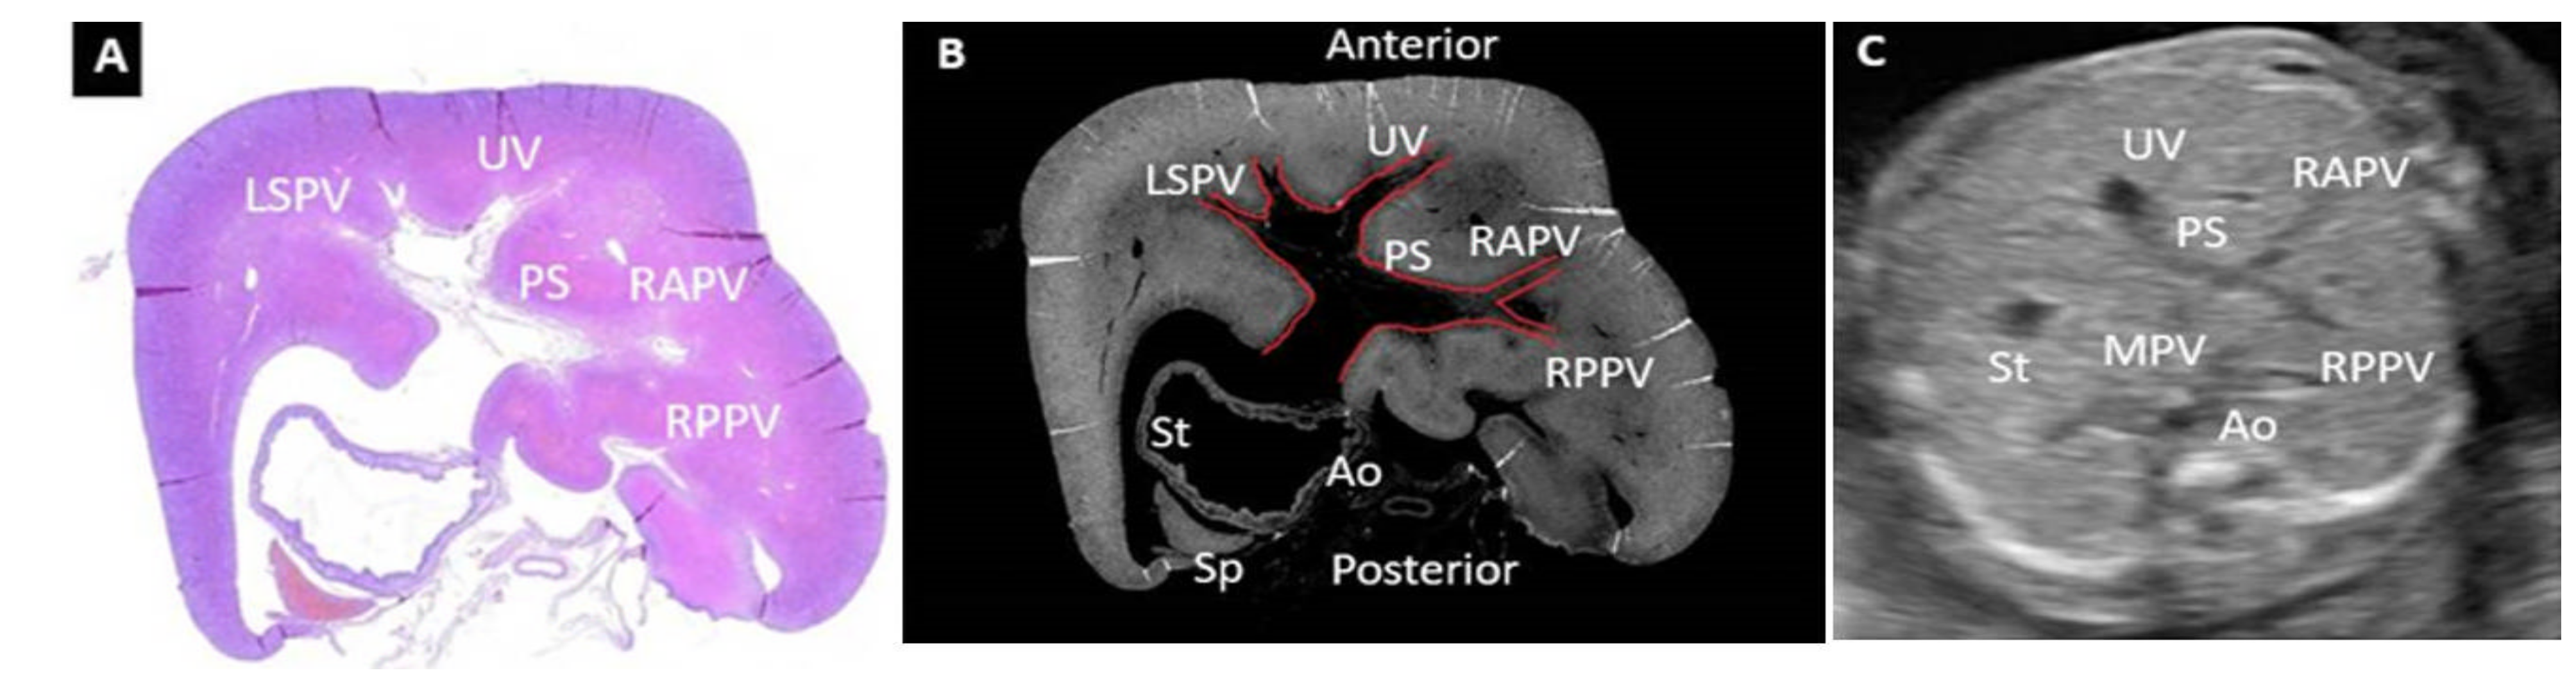

- Mavrides, E.; Moscoso, G.; Carvalho, J.S.; Campbell, S.; Thilaganathan, B. The anatomy of the umbilical, portal and hepatic venous systems in the human fetus at 14-19 weeks of gestation. Ultrasound Obstet. Gynecol. 2001, 18, 598–604. [Google Scholar] [CrossRef] [PubMed]